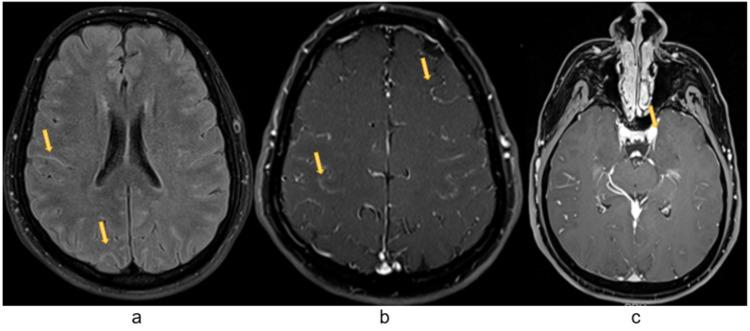

Syphilis is potentially a multisystem chronic infection caused by . Late symptomatic neurosyphilis has been less reported in developed countries, most often seen in untreated patients or in patients with HIV coinfection. We present a case of complicated neurosyphilis with widespread neurological involvement (dementia paralytica, tabes dorsalis, leptomeningitis and left oculomotor nerve involvement) presenting in the 21st century in an urban area of a well-developed European country in an HIV-negative patient.